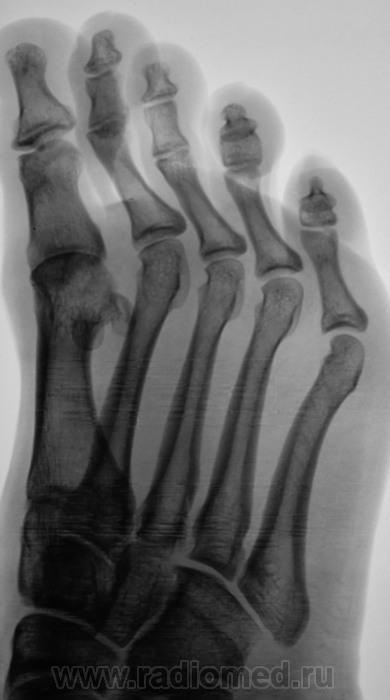

Пол пациента: Женский пол Тип патологии: Другое Область исследования: Скелетно-мышечная система Методы исследования: Rg Боли в стопе. Направлен на рентгенографию стопы. https://radiomed.ru/sites/default/files/styles/case_slider_image/public/user/12/2.201201010085.jpg?itok=dJXkcu51 https://radiomed.ru/sites/default/files/styles/case_slider_image/public/user/12/3.201401050084.jpg?itok=IXpYjiPy https://radiomed.ru/sites/default/files/styles/case_slider_image/public/user/12/4.201401050086.jpg?itok=HhXvQ302 ID:34659 Чт, 09/01/2014 - 19:39 #1 Сергей Кузьминов Не на сайте Был на сайте: 1 год 2 недели назад Зарегистрирован: 06.10.2012 - 15:51 Публикации: 11813 Назову неполным вывихом в первом плюстнефаланговом суставе. Чт, 09/01/2014 - 19:41 #2 pumpan86 Не на сайте Был на сайте: 9 лет 12 месяцев назад Зарегистрирован: 03.01.2012 - 10:49 Публикации: 60 Сергей Кузьминов wrote: Назову неполным вывихом в первом плюстнефаланговом суставе. +1. Он же подвывих.

Назову неполным вывихом в первом плюстнефаланговом суставе.